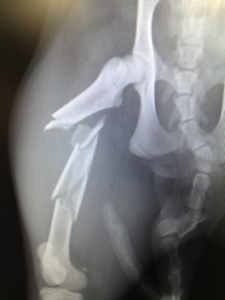

主訴:右後肢を完全に着かないとのことでかかりつけの病院を受診、レントゲン検査にて右後肢大腿骨の完全粉砕骨折と診断され、当病院を紹介され来院されました。 当病院のレントゲン検査でも右大腿骨粉砕骨折が確認されたため、飼い主様にプレートによる固定手術をおすすめし、希望されたため手術行いました。

骨片が5つ以上あり、複雑骨折と診断

骨折を確認